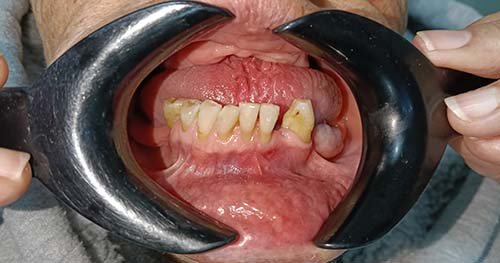

Para el cuidado después de una extracción dental, debes aplicar hielo, comer dieta blanda y fría, no fumar ni enjuagarte la boca enérgicamente durante las primeras 24 horas, y mantener una buena higiene a partir del día siguiente. También es fundamental tomar analgésicos según sea necesario, descansar, dormir con la cabeza elevada y seguir las instrucciones específicas de tu dentista.